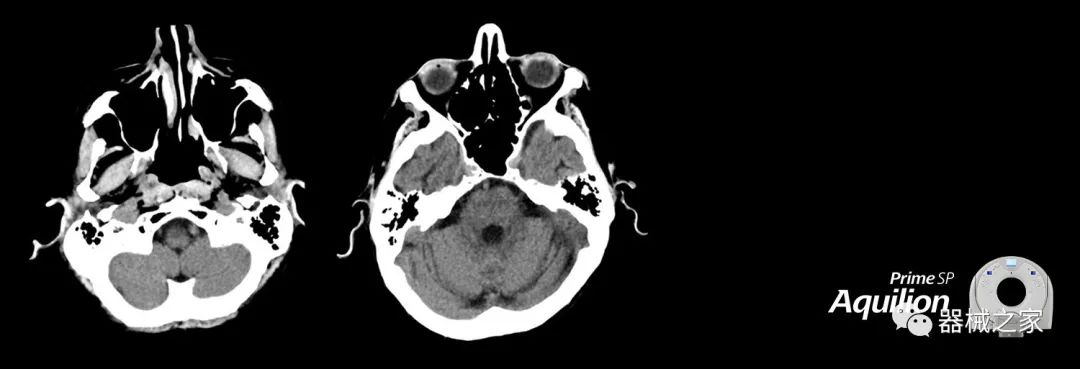

在以患者為中心的放射腫瘤學(xué)領(lǐng)域,計算機斷層掃描(CT)的可訪問性,可重復(fù)性和靈活性至關(guān)重要。為了建立這些價值,佳能醫(yī)療系統(tǒng)美國公司現(xiàn)在正在擴大其放射腫瘤學(xué)CT模擬產(chǎn)品,包括Aquilion Prime SP和Aquilion Lightning 80高級CT系統(tǒng)。除了Aquilion LB之外,Aquilion Prime SP和Aquilion Lightning 80現(xiàn)在還包括放射治療(RT)選項,可為腫瘤學(xué)規(guī)劃提供高質(zhì)量的CT成像和精密工具。

Aquilion Prime SP使設(shè)施能夠處理具有挑戰(zhàn)性的案例,同時為員工提供快速,靈活和高效的解決方案。

佳能醫(yī)療的Aquilion Lightning 80掃描儀還以緊湊,經(jīng)濟的包裝提供高質(zhì)量的成像。Aquilion Lightning 80旨在可靠,高效地運行,在繁忙的環(huán)境中生成高質(zhì)量的圖像。

兩個CT系統(tǒng)均采用0.5 mm x 80排PUREViSION探測器技術(shù)(可配置并從80-160現(xiàn)場升級),78 cm孔徑,50 cm視野,AIDR(自適應(yīng)迭代劑量減少)3-D和SEMAR(單個)能量金屬神器減少)技術(shù)。